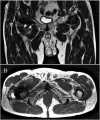

Methods: Ninety-nine patients with 134 hip articulations, 71 MoM THA/RHA and 63 MoP THA participated in a cross-sectional study at XXX University Hospital, Denmark, at mean 7.3 (range: 0.4-21.7) years after surgery. Patients' daily PA was monitored during a two-week period using a triaxial accelerometer. Metal artefact reduction sequence magnetic resonance imaging scans, estimation of serum-ion concentrations of chromium and cobalt and the Copenhagen Hip and Groin Outcome Score (HAGOS) questionnaire were completed on Day 14.

Results: Patients with a pseudotumour who underwent MoM THA/RHA had a higher average cadence of median 101.4 [interquartile range (IQR: 95.5-105)] steps/min than patients without a pseudotumor, median 96.7 (IQR: 92.2-103) steps/min (p = 0.02). Serum-ion concentrations of chromium and cobalt were higher in patients with a pseudotumour who underwent MoM THA/RHA, median 2.57 (IQR: 1.4-3.4) μg/L and 1.80 (IQR: 1.2-2.6) μg/L, respectively, than in patients without a pseudotumour, median 1.85 (IQR: 1.1-3.2) μg/L and 1.34 (IQR: 0.9-2.2) μg/L in MoM THA/RHA (p = 0.04 and p = 0.03). There was no statistical difference in these parameters between patients with and without a pseudotumour who underwent MoP THA. Daily PA levels of patients who underwent MoM THA/RHA were significantly correlated with serum-ion concentrations of chromium (p = 0.0002, r = 0.44) and cobalt (p = 0.005, r = 0.34), whereas no correlations were seen among patients who underwent MoP THA (p > 0.12).